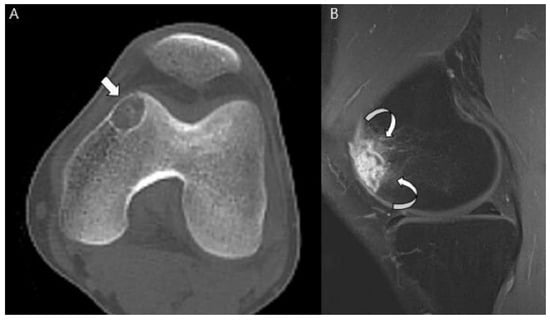

3.1. Distinction between Enchondroma and ACT

3.2. Biopsy or Follow-Up? Questions for Incidental Cartilage Lesions in the Long Bones

3.3. Distinction between ACT/CS1 and High-Grade Chondrosarcoma